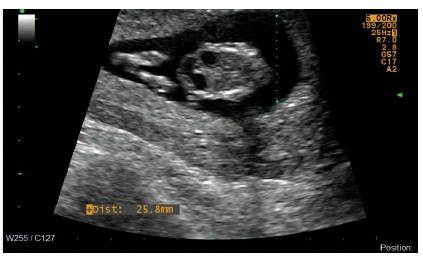

Una paciente de diecinueve años primigestante ingresa al servicio de urgencias de Ginecología y Obstetricia del Hospital Militar Central con un embarazo de 12 y 1/7 semanas, con un cuadro clínico compatible con una amenaza de aborto; sin antecedentes personales o familiares de relevancia y sin exposición a ningún teratógeno conocido. Se solicita ecografía obstétrica en la que se reporta un feto con LCC de 58 mm y, como hallazgo incidental, la presencia del signo de doble burbuja intraabdominal, compatible con atresia duodenal. Se remite al paciente al servicio de Medicina Materno Fetal de la institución (Figura 1).

Posteriormente, en la ecografía de tamizaje 11-13,6, se reconoce nuevamente el signo de doble burbuja abdominal en un feto con Lcc de 64 mm, arteria umbilical única, con hueso nasal presente y una sonolucencia nucal de 1,1 mm.